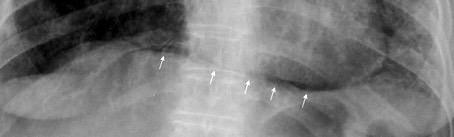

Diafragma “colgante” (“dangling sign”)

(“Dangling sign”)

Diafragma discontinúo Herniación de la grasa omental

Desser TS et al.The dangling diaphragm sign: sensitivity and comparison with existing CT signs of blunt traumatic diaphragmatic rupture. Emerg Radiol 2010